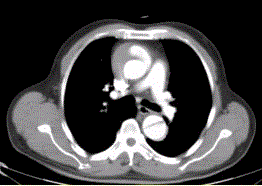

问题 患者男,67岁,高血压病史多年,自服降压药,突发胸骨后剧烈疼痛2h,服用硝酸甘油不缓解。胸透示主动脉增宽。CT影像如下图。 本例分型属

选项 A.DebakeyI型 B.DebakeyIIa型 C.DebakeyIIb型 D.DebakeyIII型 E.StanfordA型 F.StanfordB型

答案 AE